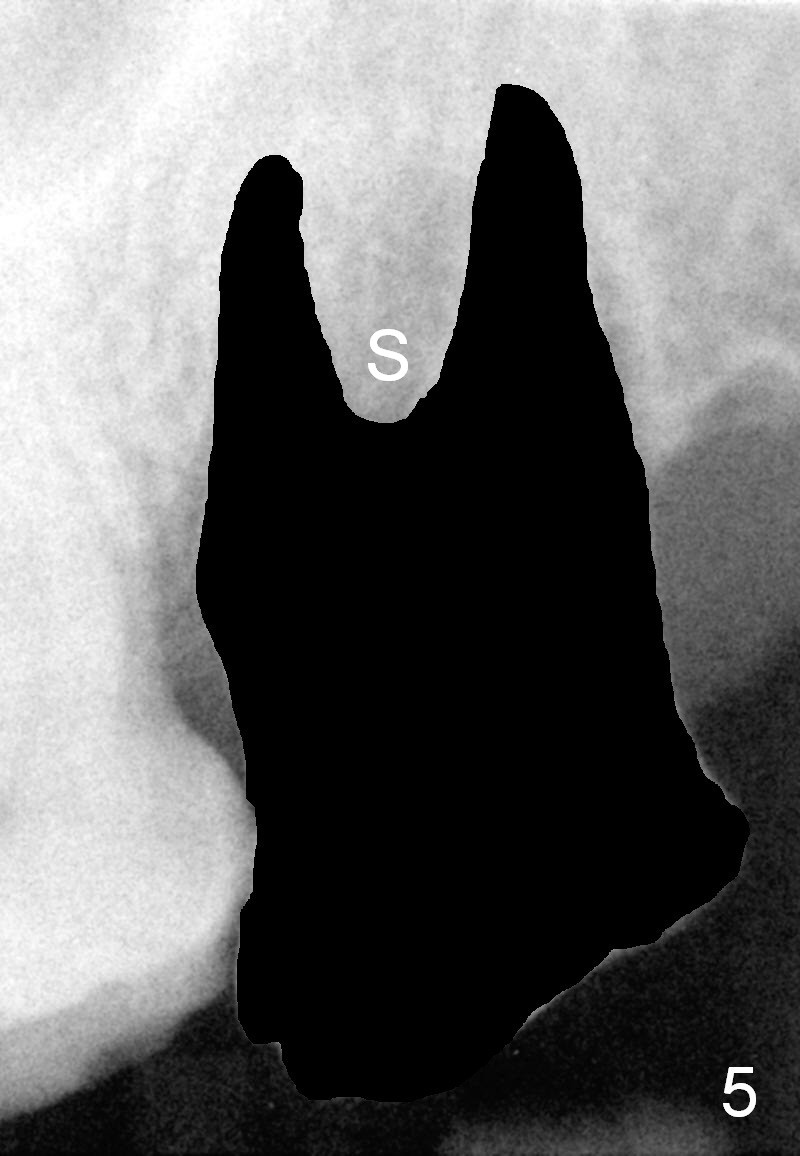

A 53-year-old man (ZB) has history of chronic periodontitis and bruxism. The tooth #18 has been extracted for a few years, while the tooth #15 is going to (Fig.1). Bone height for #15 immediate implant is not a problem (Fig.2-4; green line in Fig.2: sinus floor). After extraction (Fig.5 )socket to be treated with Clindamycin), use starter drill and a 2 mm pilot drill with stopper at 10 mm (Fig.6) on the crest of the septum (Fig.5 S). PA is taken with a parallel pin. Adjust the length accordingly. Subsequent osteotomy will be carried out with drills with stopper at 50 RPM. In brief, the implant does not need to be large. It should be placed as deep as possible (1-2 mm subcrestal mesially and/or distally), since the vertical height in the posterior region is limited. The margin of a cemented abutment is to be slightly subgingival. Use an immediate provisional to close socket gap, while to keep abutment margin from the gingiva. Use Collagen dressing before and after bone graft.